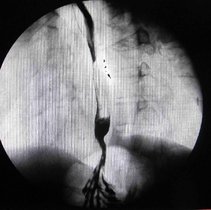

返流性食管炎